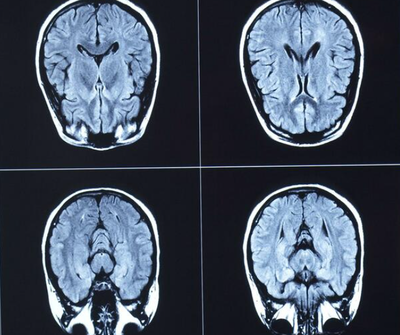

医師らがカナダのニュー・ブランズウィック州で原因不明の病気が拡大しているのを確認した。ニューヨーク・タイムズ紙が報じた。

新たな一連の神経障害を患った初の患者らが国内で確認されたのは2015年のことだったが、しかし、その際には患者数は最大で50人まで増加し、6人の死亡者が報告されている。すべての期間を通じ、ニュー・ブランズウィック州に隣接する2つの地域で感染者が発生していることが注目されている。

原因不明の病気の症状としては、急速に痴呆が進行することとさまざまな精神医学的症状があげられる。また、患者らは不眠や運動障害、視覚機能障害を訴えている。医師らは、この病気を分類することができていないが、それは毎回、発症する症状が多種に及んでいることによる。

また、同様に死亡解剖でも病気の謎を解明することに成功していない。そのため、根拠のないままプリオン病が疑われている。現在、この病気の基本的な学説は、神経毒による中毒、特にドウモイ酸と考えられている。ドウモイ酸は、多くの藻類や甲殻類、魚類に含まれている。現在、医師らは、病気について「ニュー・ブランズウィック州の原因不明の神経病理シンドローム」と呼んでいる。